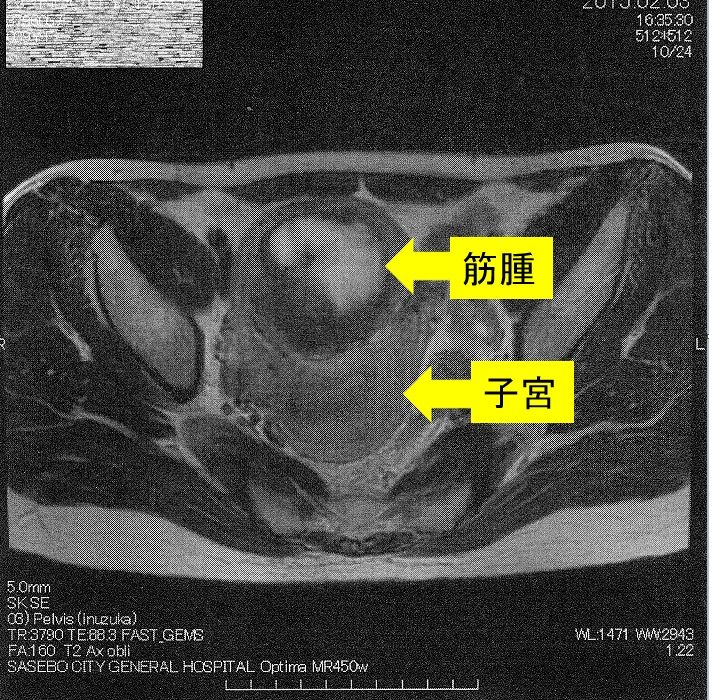

¡Ú2015ǯ2·î3Æü¡¡£Í£Ò£É¼Ì¿¿¡Û

¢¨Çò¤¤Éôʬ¤¬¶Ú¼ð¡¢¼þ¤ê¤ÎÉôʬ¤¬»ÒµÜ¤Ç¤¹¡£